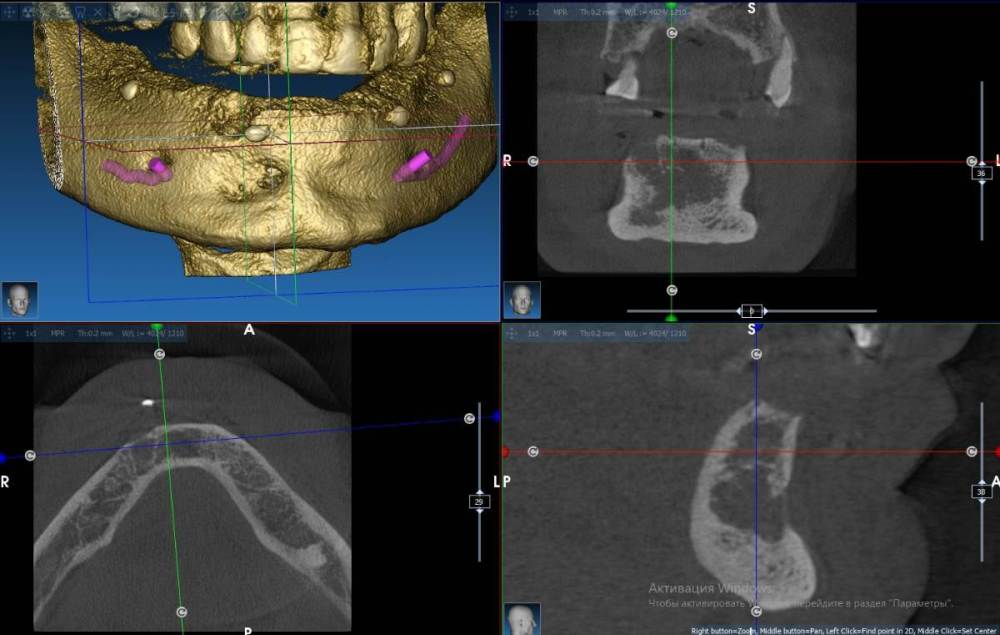

Fin Опубликовано 13 марта, 2022 Поделиться Опубликовано 13 марта, 2022 Здравствуйте коллеги. Появился очень странный вопрос. Год назад у меня был пациент - мужчина 40 лет на консультацию по имплантации все на 6 на НЧ. В процессе осмотра снимка КТ обнаружил в зоне 43 хронический воспалительный процесс. Данный процесс был прокюретажен, пациент отпущен на заживление на пару месяцев. Старый снимок Так получилось что с пациентом мы встретились только сейчас и решили продолжить наше лечение. Далее повторное КТ со скан маркерами на его съемном протезе, сделан слепок протеза- пациент отпущен. В ходе планирования шаблона я обнаружил улучшение со стороны воспалительного процесса но так же обнаружил странное образование рядом не сообщающееся со старым воспалением. Новый снимок Подскажите что это может быть т.к. вижу такое впервые. Сам думаю что скорее всего я преувеличиваю и это из-за того, что снимки сделаны на разных аппаратах, но хотелось бы услашать Ваше мнение. Ссылка на комментарий

Doctor Vlad Опубликовано 14 марта, 2022 Поделиться Опубликовано 14 марта, 2022 кортикалки то не стало в стороне от лунки. может и стоит Ссылка на комментарий

Fin Опубликовано 14 марта, 2022 Автор Поделиться Опубликовано 14 марта, 2022 3 часа назад, Doctor Vlad сказал: кортикалки то не стало в стороне от лунки. может и стоит Меня это и удивило, видимо да, все таки отправлю пациента в ЧЛХ Ссылка на комментарий